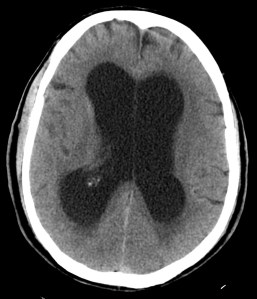

CASO 4.

Paciente de 80 años diagnósticada de melanoma que acude a por cefalea que no cede a analgesia y estupor.

Hemorragia lobar:

Las hemorragias lobulares afectan a la región cortical de cualquier lóbulo cerebral y la causa subyacente puede ser la hipertensión, un traumatismo o espontánea, donde subyace la angiopatía amiloide (ancianos) y la malformación vascular (jóvenes: MAV) principalmente. Tiene mejor pronóstico que en la afectación de los ganglios de la base y tálamo. La aplicación de contraste puede ser útil para diferenciarlas de un tumor, aunque entre sus inconvenientes cabe destacar el realce anular de los hematomas y que puede ser difícil identificar una zona tumoral de realce reducido en el seno de una hemorragia.

TAC es la prueba de elección. El extravasado de sangre se observa como un aumento de la atenuación. Existe una correlación lineal entre el hematocrito y el aumento de atenuación por sangrado (56 unidades Hounsfield aprox.)

Causas hemorrágicas de accidentes cerebrovasculares (pulsa para agrandar). Importante destacar otras causas no comentadas como las coagulopatías, la toma de anticoagulantes y los tumores (glioblastoma en adultos, meduloblastoma en niños y metástasis de coriocarcinoma, melanoma, pulmón, riñón, tiroides. Co-me pu-ri-to)